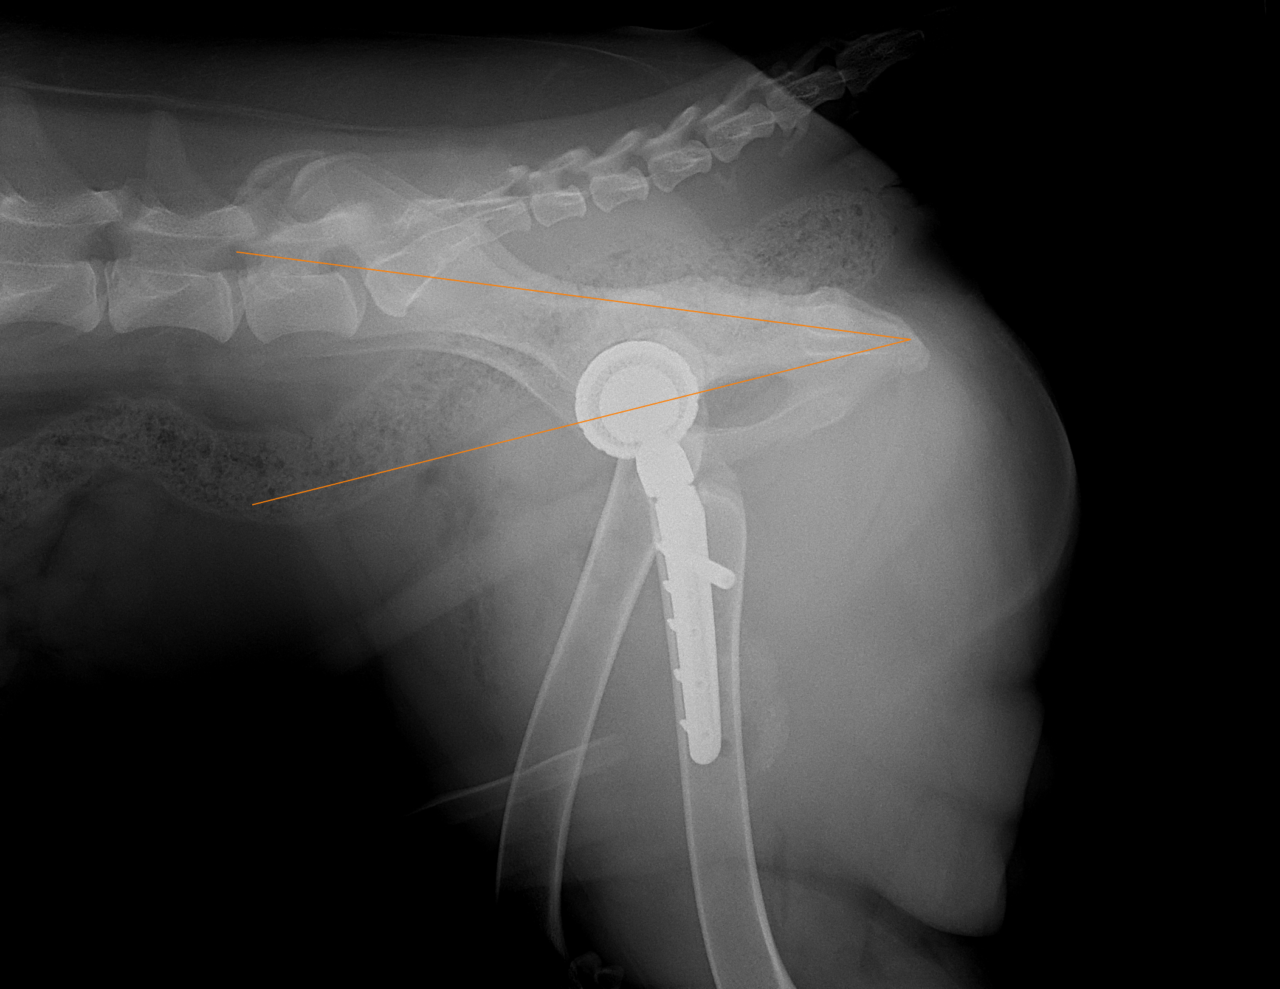

THR #24 大型犬の股関節形成不全のパピーに最も除痛効果と機能回復が期待できるトータル・ヒップ・リプレイスメントで対応しました。しばらくは安静が必要です。 症例カテゴリー 放射線治療整形外科軟部組織外科脳神経外科内科腫瘍外科救急・集中治療リハビリテーション科腫瘍内科内視鏡科脳神経科呼吸器外科中医・漢方猫の腎移植循環器科